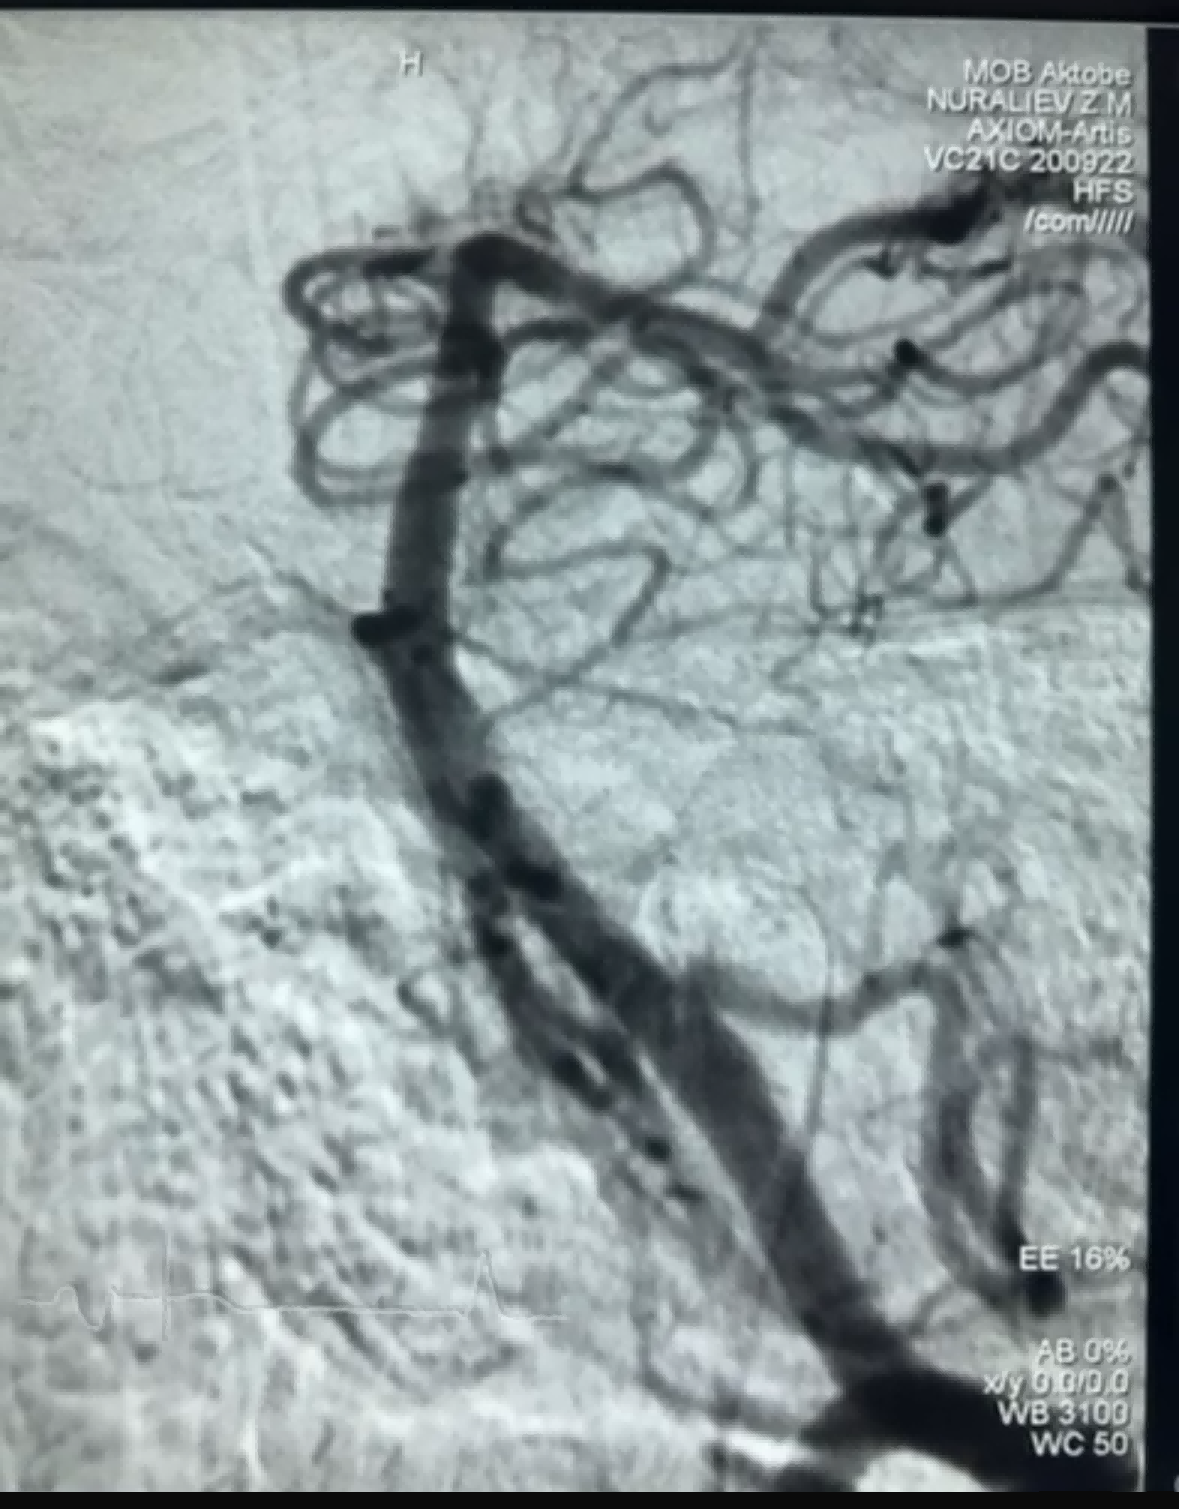

Onlangs was er een succesvolle trombectomie met behulp van de Dredger Stent Retriever van NeuroSafe Medical Co., Ltd. De Dredger Stent Retriever heeft een niet-invasieve zachte punt, die het risico op intimale schade aanzienlijk vermindert, en heeft een uniek speciaal gevormd gatontwerp dat bloedstolsels voornamelijk opvangt door de openingen af te klemmen.